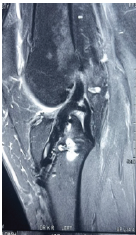

Simultaneous ACL Reconstruction and MCL Reconstruction in Patients with High BMI using Modified Lind Technique

J B Vadhiraj Krishna , Mohammed Aquib Shakeel , A G Rakshith , Rajkumar S Amaravathi , G M Sandesh , Anoop Pilar

………………………………p.334-341